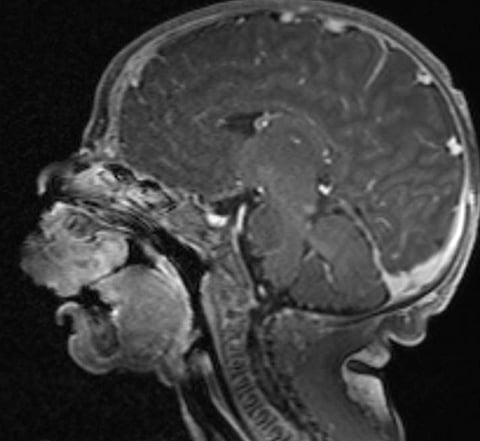

نجح فريق طبي متخصص في جراحة الفم والوجه والفكين بمدينة الملك سعود الطبية، عضو تجمع الرياض الصحي الأول، في إجراء عملية جراحية دقيقة لإزالة ورم خلقي حميد نادر من الجهة الأمامية لعظام الفك العلوي لمولودة تبلغ من العمر أربعة أيام.

وقد شكلت هذه الحالة محورًا لدراسة علمية متخصصة أجراها الفريق بقيادة الدكتور خالد المطيري، استشاري جراحة الفم والوجه والفكين، حيث تم توثيق تفاصيل الحالة بدءًا من التشخيص الدقيق، مرورًا بخطة التدخل الجراحي، وصولاً إلى النتائج السريرية طويلة المدى.

وسلطت الدراسة الضوء على التحديات التشخيصية والعلاجية لمثل هذه الحالات النادرة، ولا سيما أن الورم تسبب في إعاقة الرضاعة، وقد يُشكّل خطرًا أكبر في بعض الحالات الأخرى إذا أثّر على مجرى التنفس، ما يؤكد أهمية التدخل الطبي السريع.

وأشار الفريق إلى أن هذا النوع من الأورام يُعد من الحالات شديدة الندرة، حيث تُقدر نسبة حدوثه بـ6 حالات فقط لكل مليون ولادة، كما وثّقت الأدبيات العلمية أقل من 250 حالة حول العالم منذ اكتشافه للمرة الأولى عام 1871م.